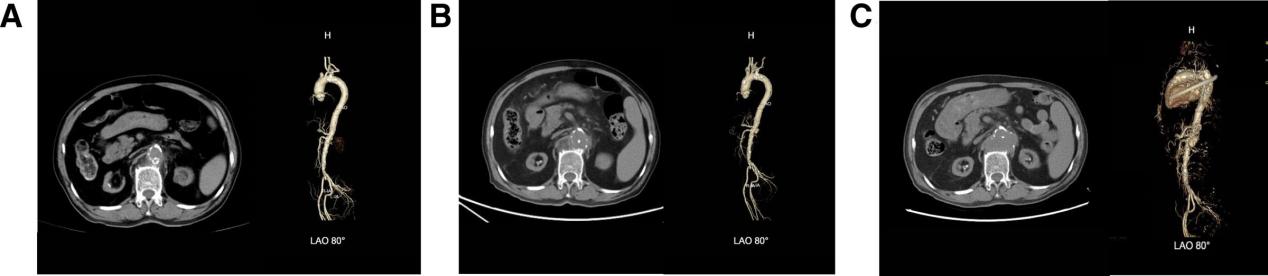

入院初始实验室检查:白细胞计数显著升高(23.95×10⁹/L),中性粒细胞占比 95.1%,C 反应蛋白(196.06 mg/L)及降钙素原(21.15 ng/mL)明显增高,提示存在严重的炎症反应。入院血培养后证实金黄色葡萄球菌阳性。胸腹部计算机断层扫描血管造影显示腹主动脉局灶性溃疡,周围少量渗出,并伴有胸主动脉和腹主动脉的动脉粥样硬化改变及双侧肾动脉狭窄(图1A)。

图1 计算机断层扫描血管造影(CTA)系列影像显示主动脉溃疡进展过程:(A)2024 年 10 月 10 日 CTA,可见主动脉局部溃疡,伴主动脉周围渗出;(B)2024 年 10 月 22 日复查 CTA,溃疡进展为穿透性,直径由 5 mm 扩大至 11 mm,炎症反应加重;(C)2025 年 1 月 2 日复查 CTA,考虑腹主动脉多发穿透性溃疡,伴周围巨大血肿形成,较前次影像学检查呈显著进展

患者初始诊断为脓毒症、尿毒症和高钾血症,并开始广谱抗生素治疗:美罗培南0.5g每12小时静脉注射,联合利奈唑胺0.6g每12小时口服。在血培养鉴定出甲氧西林敏感金黄色葡萄球菌(MSSA)后,调整为万古霉素 0.5g 静脉滴注,每 8 小时 1 次。尽管炎症标志物初期有所改善,但约2周后的随访计算机断层扫描血管成像显示腹主动脉溃疡进展,伴周围渗出性改变(图1B)。抗生素方案随后调整为哌拉西林-他唑巴坦4.5g每12小时静脉注射,联合莫西沙星0.4g每日口服。整个病程中抗生素使用的时间线如图2所示。

出院后,患者按要求在门诊随访。2025年1月2日最后一次随访检查显示,与之前相比,患者溃疡显著进展,并伴有巨大血肿(详见图1C)。目前,患者溃疡状况极不稳定,可能随时导致血肿破裂和出血。尽管给予了适当的抗生素治疗和全面的支持治疗,持续性腹主动脉溃疡仍具有发生致命性并发症(如破裂)的风险,这可能意味着预后不良。